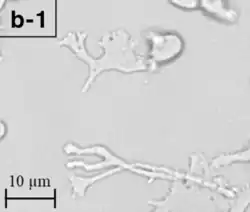

Trophozoite (active) form of Balamuthia mandrillaris

B. mandrillaris is a free-living, heterotrophic amoeba, consisting of a standard complement of organelles surrounded by a three-layered cell wall (thought to be made of cellulose or a similar polysaccharide[8]), and with an abnormally large cell nucleus. On average, a Balamuthia trophozoite is about 30 to 120 μm in diameter. The cysts fall around this range, as well.[9]

Balamuthia's lifecycle, like the Acanthamoeba, consists of a cystic stage and a non-flagellated trophozoite stage, both of which are infectious, and both of which can be identified in the brain tissue on microscopic examination of brain biopsies performed on infected individuals. The trophozoite is pleomorphic and uninucleated, but binucleated forms are occasionally seen. Cysts are also uninucleated, possessing three walls: an outer thin irregular ectocyst, an inner thick endocyst, and a middle amorphous fibrillar mesocyst.[10]

Biopsies of skin lesions, sinuses, lungs, and the brain can detect of B. mandrillaris infection. The amoeba cannot be cultured on an agar plate coated with E. coli because, unlike Naegleria or Acanthamoeba, Balamuthia mandrillaris does not feed on bacteria. Instead, Balamuthia must be cultured on primate hepatocytes or human brain microvascular endothelial cells.[15] Formalin-fixed paraffinized biopsy specimens may indicate Balamuthia trophozoites in the perivascular space. The cysts can be visualized by calcofluor white, which binds to polysaccharides on the cyst wall. Trophozoites appear circular during infection.[14]